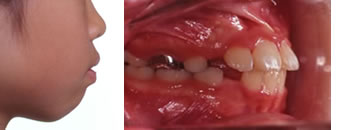

■治療開始

治療開始時は、7歳9ヶ月です。指しゃぶりの癖があり、前歯が前方に大きく傾いて上顎前突(出っ歯)になってしまったケースです。